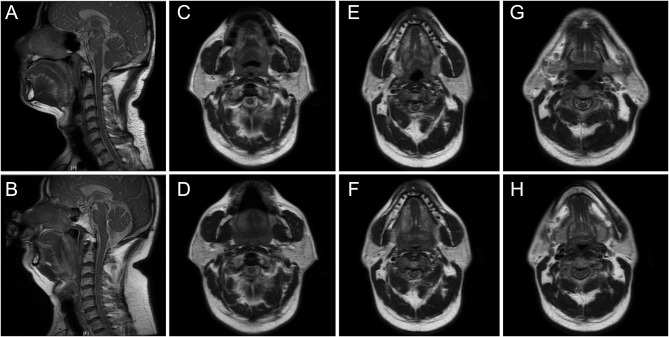

Patients and methods: Patients with OSAHS diagnosed by polysomnography (PSG) from February 2025 to March 2025 were included in this study, and UADMR was performed to detect the obstructive levels (palatopharyngeal level, root of tongue level, and epiglottic level) and assess the degree of obstruction at the root of the tongue and epiglottic levels. Subgroup analyses were performed according to different obstructive characteristics and the results of UADMR were assessed for correlation analysis with the results of PSG or manual titration of positive airway pressure. This study used Müller maneuver to simulate the airway collapse during sleep.

Results: A total of 34 OSAHS patients were included in this study. It was observed that the hypopnea index, apnea hypopnea index, and tongue axial change ratio were significantly higher in OSAHS patients with multiple layers of airway obstruction than in those with palatopharyngeal obstruction only. The anteroposterior diameter change ratio at the level of the root of the tongue and the area change ratio at the level of the epiglottis in patients with OSAHS were positively correlated with the results of the PSG, and the tongue axial change ratio was positively associated with the results of the manual titration of positive airway pressure.